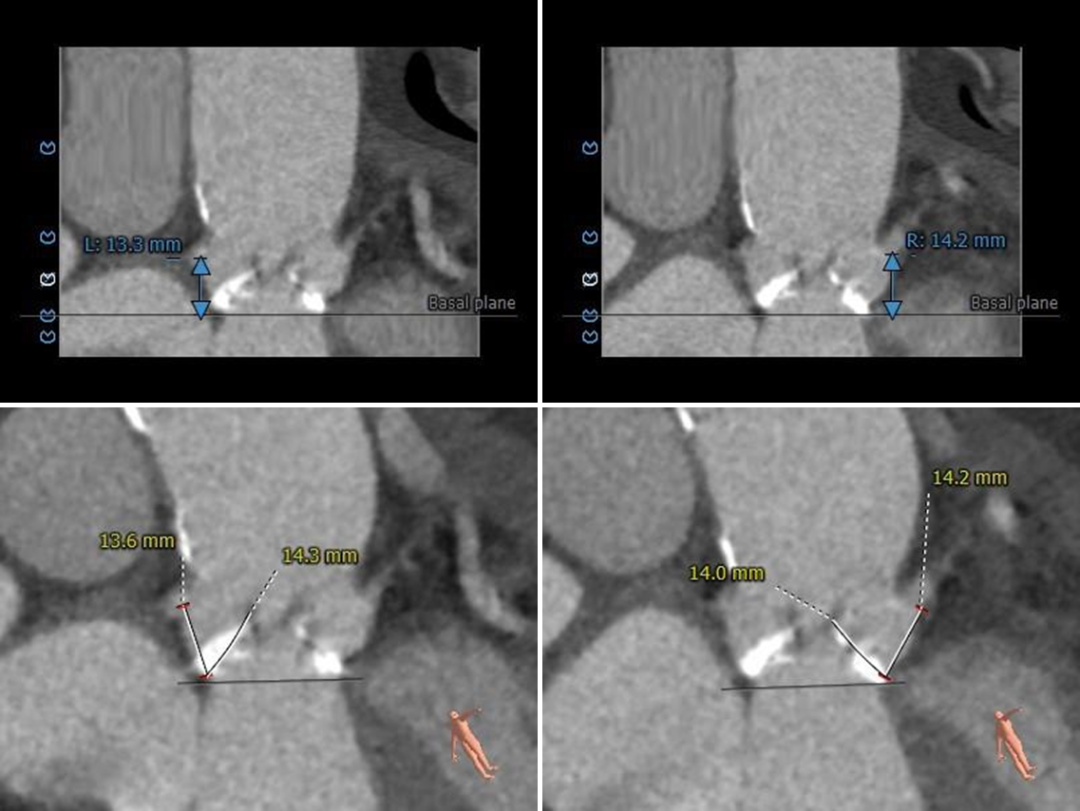

冠脉测量

冠脉开口高度可,切线位测量左窦瓣叶略长于左冠开口

该病例为三窦式,无冠窦先天发育畸形,窦内空间小并存在嵴样间隔,钙化主要分布在左右窦接近窦底位置并向下延伸,左窦瓣叶略长,可疑阻挡风险,术中需加以关注。

左右冠开口高度可,左窦瓣叶略长于左冠开口,右窦瓣叶未见冗长,术中需关注冠脉情况,必要时冠脉保护;